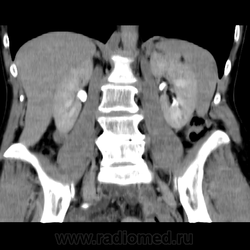

Обнаружилось небольшое образование низкой плотности, с достаточно ровными, четкими контурами парааортально справа около ножки диафрагмы на уровне тела L1 позвонка.

При нативе плотность 6HU, паренхиматозная - 18-20HU, экскреторная (15 минут) - 60-65HU.

Выкладываю по очереди срезы на одинаковых уровнях, сначала паренхиматозная, потом отсроченная фазы.

можете выложить более тонкии срезы на уровне данного образования аксиальные и коронольные срезы в венозную фазу???

или я придираюсь или там что-то под правой почкой есть!!! сканограм побольше бы?!!!! можно еще немного кадров корон в венозную фазу выложить????

но все же если можно выложите побольше корон в венозную фазу?!